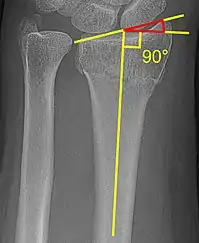

Radial inclination

The radial inclination of a distal radius fracture is shown in red in image at right. The angle is measured between:[4][5]

- A line drawn between the distal ends of the articular surface of the radius on an AP view of the wrist.

- A line that is perpendicular to the diaphysis of the radius.

Radial inclination is normally 21-25°.[6]